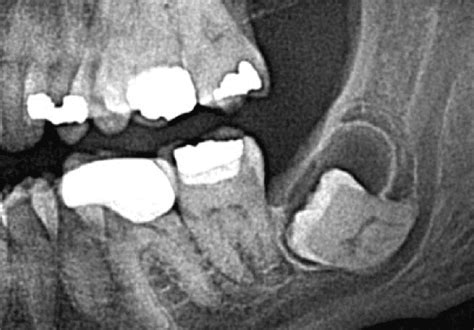

El quiste dental puede deberse a distintos motivos, pero todos ellos tienen algo en común: implican infección en el diente o en los tejidos próximos a este. Generalmente los quistes dentales se observan a través de una radiografía panorámica o una radiografía 3D que es mucho más precisa y exacta.

- Desarrollo de un diente: el quiste puede darse cuando erupciona una nueva pieza dental y no dispone del espacio suficiente, como sucede a menudo con las muelas del juicio.

Ante la presencia de los síntomas antes descritos, se debe recurrir a un profesional de la salud dental para que determine cuál es el diagnóstico correcto. Para detectarlo, de hecho, el médico necesitará una radiografía panorámica y/o periapical.

Estos estudios determinarán el tamaño del quiste, su origen, la posición, el estado del diente y de la encía y cómo afecta a los dientes cercanos a él. En base a esto se puede establecer la manera de extirpar el quiste que será diferente en cada caso.